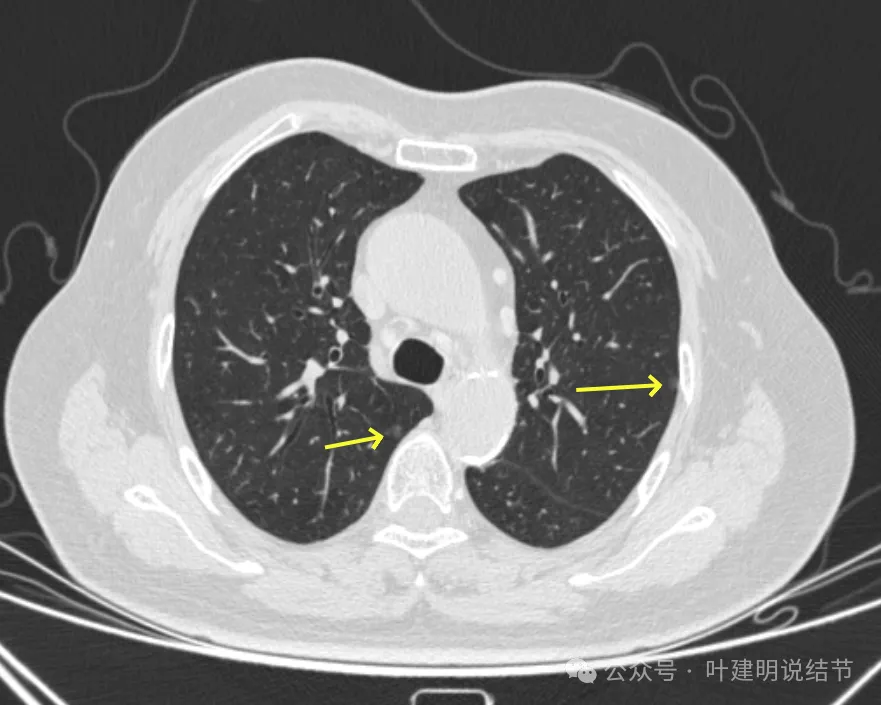

病灶11-14:两肺淡磨玻璃结节,轮廓较清。

病灶15-18:右上叶淡磨玻璃结节,轮廓较清,有的界限稍不清。

病灶19-20:两肺淡磨玻璃结节,轮廓较清,小但边界清楚。

病灶21-22:两肺淡磨玻璃结节,轮廓较清。